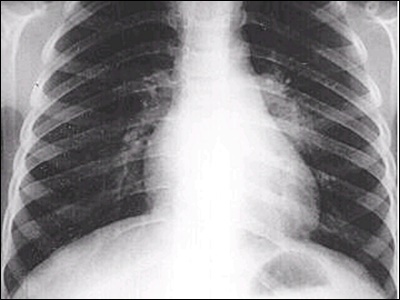

결핵 진단을 위해서는 피부 검사, 가슴 X-선, 결핵균 검사 등의 검사가 필요합니다. 이러한 검사를 통해 정확한 진단을 받을 수 있습니다.